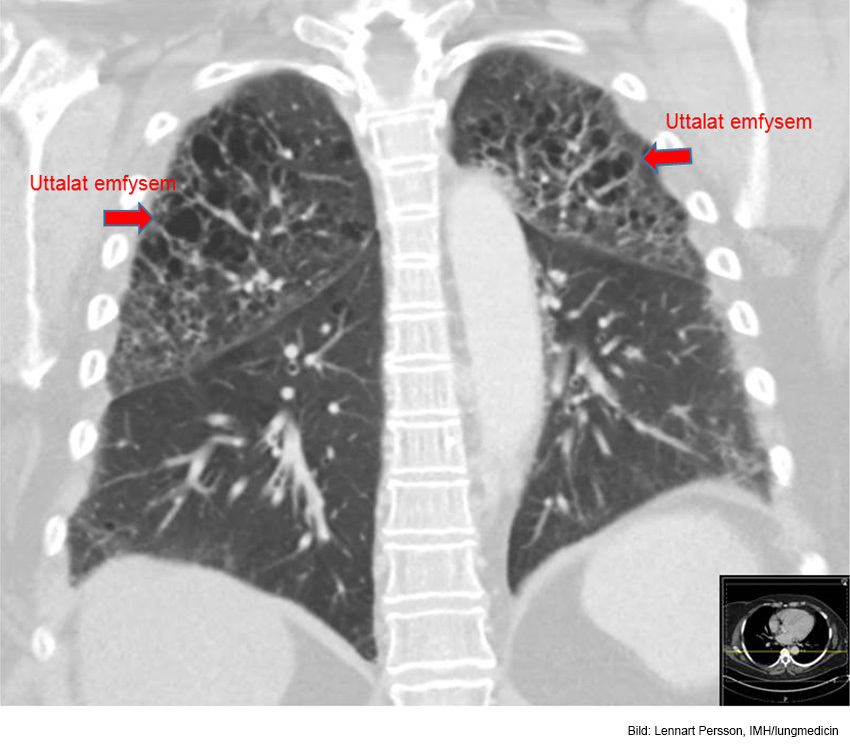

Q

Vad ser du här?

A

Uttalat emfysem inom bägge ovanlober. Basalt ventralt i höger lunga finns en liten tumörmisstänkt förändring.